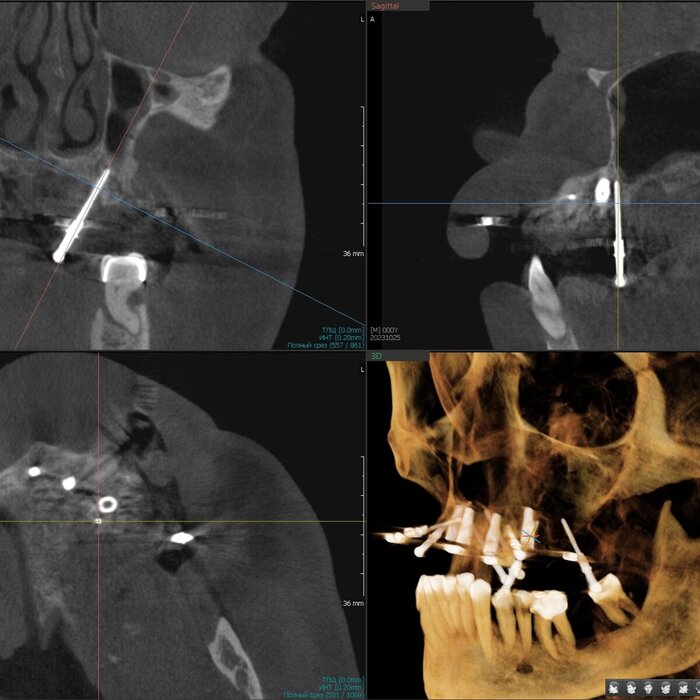

Посмотрим срезы.

Пародонтит.

Зубы цепляются за кость верхушками корней.

Пародонтит.

Куда ни глянь - одна картина.

Пародонтит.

Деструкция кости капитальная.

Пародонтит + периодонтит.

Хуже пародонтита может быть только присоединившийся к нему периодонтит (воспалительный процесс на верхушке корня/корней, в народе "киста") - вот уж где разрушение кости глобальным образом проявляется.

Периодонтит.

Кортикальные пластики утеряны, жаль.